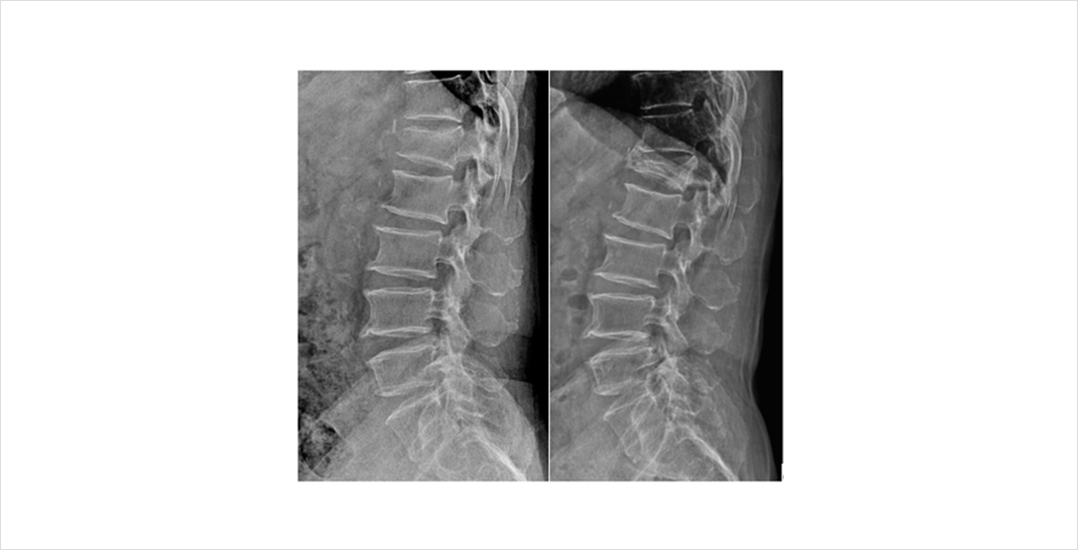

골다공증성 척추압박 골절이 제대로 치료되지 않는다면 척추체의 붕괴와 더불어 이로 인한 척추 후만 변형이 발생할 수 있습니다. 척추 후만 변형은 골다공증성 척추 압박 골절로 인한 척추체의 붕괴가 주로 척추의 앞부분에서 나타나기 때문입니다. 이는 골절의 회복 후에도 지속되는 허리통증 등의 후유증을 야기할 수 있습니다.